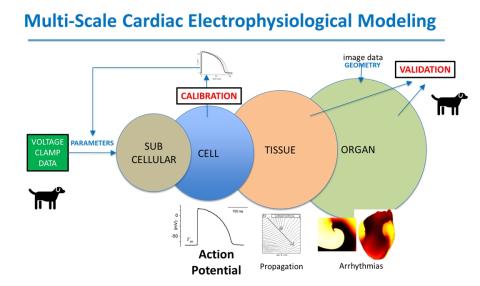

Cardiac Action Potential Model of the Dog

Categories:

Computer Model

An implementation of a canine action potential model appropriate for comprehensive parameter sensitivity analysis and uncertainty quantification

Program Areas:

Cardiovascular